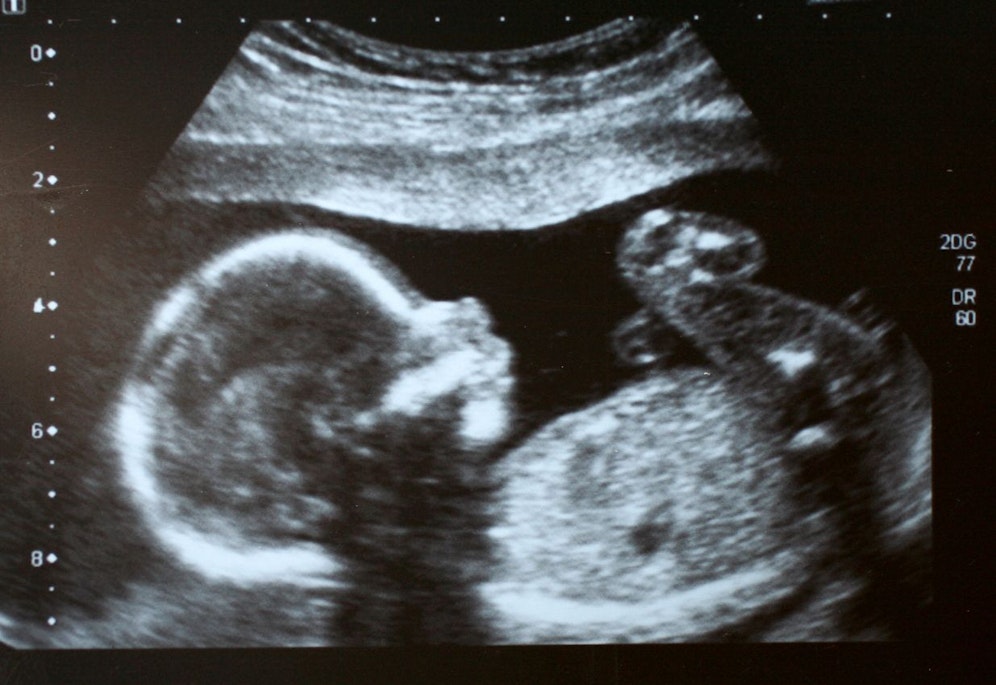

Eine außergewöhnliche Nachbildung dessen, was ein Baby im Mutterleib hören kann, hat Menschen in den sozialen Medien zu Tränen gerührt. Der Schöpfer Dimitris Chronis Animus Mentis Productions teilte die Simulation auf YouTube, wo sie tausendfach gesehen wurde. Die Simulation demonstriert nicht nur, was Babys hören können, sondern auch, wie sie Musik hören.

So wurde Video gemacht

Aber wie wurde dieses einzigartige Geräusch nachgebildet? Der Video-Creator erklärt: "Ich habe es geschafft, einen Ambisonic-Recorder in einen mit Wasser gefüllten Kübel zu stellen und den Klang eines afrikanischen Schlafliedes über einen Bluetooth-Lautsprecher aufzunehmen. "Daher ist es mir gelungen, die fließende Bewegung des ambisonischen Mikrofons bzw. des Fötus durch eine Ambix-Aufnahme einzufangen. Ich habe die Aufnahme mit Equalizer weiterbearbeitet und auch ein Ultraschallbild des Herzens eines Fötus verwendet."